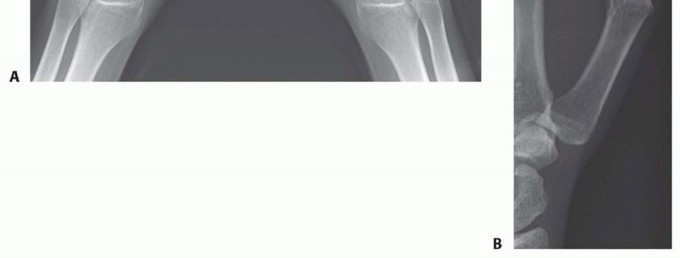

P.1057Radiographic evaluation includes a posteroanterior (PA) 30-degree oblique stress view, lateral view, and a Robert (pronated anteroposterior [AP]) view (FIG 1).Osteoarthritis may be confined to the TM joint, or it may involve the pantrapezial joint complex. Indeed, the staging system described by Eaton and Littler describes four stages:Stage 1: a normal joint with the exception of possible widening from synovitis Stage 2: joint space narrowing with debris and osteophytes smaller than 2 mm Stage 3: joint space narrowing with debris and osteophytes larger than 2 mmStage 4: scaphotrapezial joint space involvement in addition to narrowing of the TM joint

FIG 1 • AP (A) and lateral (B) preoperative thumb radiographs.